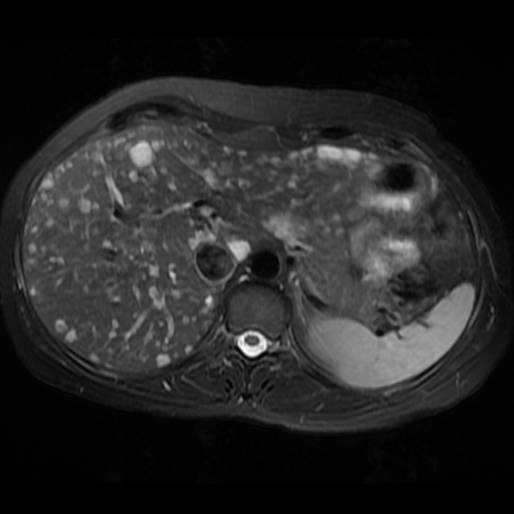

- Diaqnozu dəqiqləşdirmək üçün Qc venaları yoxlanılmalıdır. Bunun üçün dopler USM, KT-angioqrafiya, MRT-angioqrafiyalar və ya kontrastlı venoqrafiya edilir.

- Görüntüləmədə Qc venalarının trombotik tutulması diaqnozu dəqiqləşdirən əlamətdir.

- MRT-angioqrafiya;

Qaraciyər venalarının görünməməsi, kontrastlaşmaması və ya trombla tıxanması.

- Görüntüləmədə qaraciyər venalarının tıxanması, I seqment hipertrofiyası ola bilər (xroniki forma);